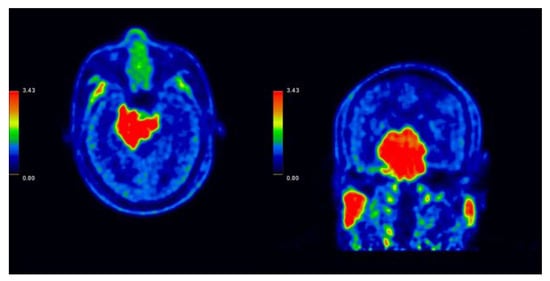

2.4. Case 284

| 284 | 28 December 2022 | 2369 | 16.83 | 9.61 | 11.29 | SD | 10 January 2023 | 2 |

| 284 | 69/Male | Atypical meningioma | Right SC sinus | 7.07 | RT + OP + ChemoT |